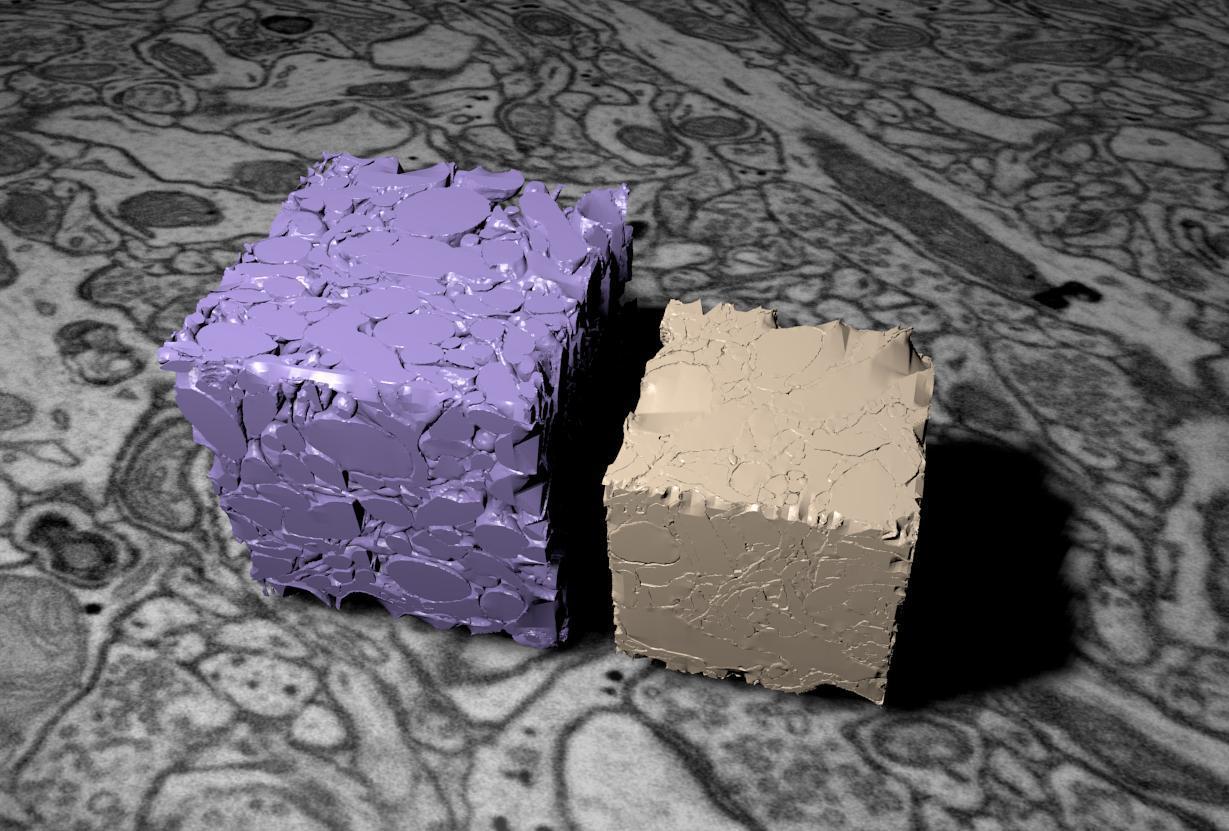

Grâce aux photographies en microscopie électronique 3D, les chercheurs ont pu comparer les images du cerveau gelé avec celles du cerveau fixé chimiquement. L’analyse a montré que ce dernier est beaucoup plus petit en volume et qu’il présente une perte significative d’espace entre les neurones. Les informations se transmettraient donc très rapidement. Par ailleurs, il apparaît que le nombre de connexions entre les neurones, aussi appelées synapses, est plus faible dans celui-ci que dans le cerveau cryofigé. Il est donc possible que la fixation chimique en détruise un nombre important. Enfin, les chercheurs ont également observé que les astrocytes, des cellules entourant les neurones, sont bien moins connectées aux cellules neuronales et aux vaisseaux sanguins.

Crédit : © Graham Knott/EPFL

Pour modéliser la compaction du cerveau, les chercheurs ont utilisé ces deux cubes. Le violet (à gauche) représente le volume réel du cerveau, conservé par la cryofixation, et le cube beige (à droite) illustre le rétrecissement provoqué par l'aldéhyde.